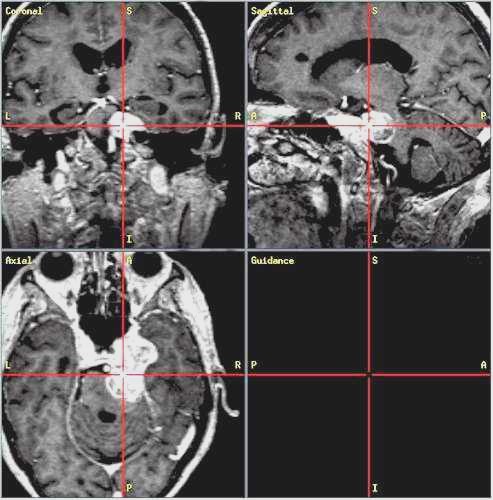

Glioma

ad alto grado di malignità (Glioblastoma) |

Lesioni caratterizzate da un accrescimento veloce con infiltrazione del tessuto cerebrale attiguo e diffusione a distanza di cellule maligne.

Scopo della chirurgia è ridurre macroscopicamente la massa tumorale per facilitare ulteriori trattamenti (principalmente radio - chemioterapia mentre altri protocolli terapeutici sono ancora in fase di studio).

In queste lesioni la loro conformazione anatomica, praticamente sempre di tipo II (Daumas-Duport) non ha un ruolo così dirimente nell'indicazione chirurgica poiché il comportamento biologico è sicuramente il fattore più importante.

RM:

glioma con segni di trasformazione maligna